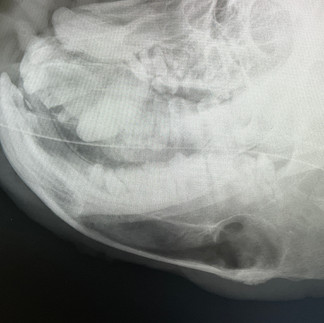

血液検査を実施、鎮静下で歯のレントゲン検査を行いました。

x線検査:犬歯歯根周囲に透過性亢進の嚢胞形成

診断:左下顎犬歯の歯根膿瘍

犬歯の歯根は膿瘍が多量にあり、嚢胞が形成されていました。